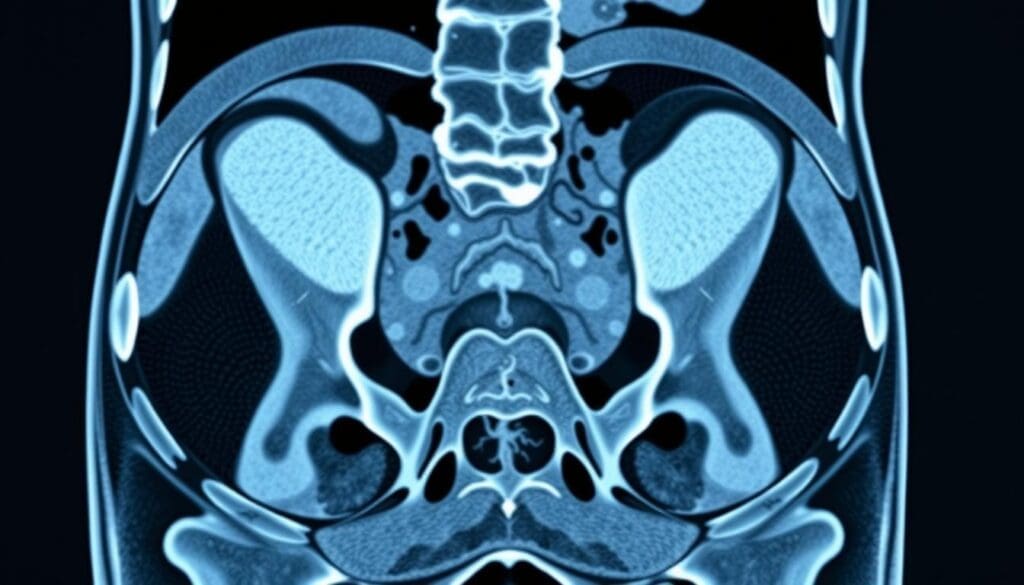

CT scans are key in finding inguinal hernias. They use X-ray technology to show the body’s inside. This helps see the small details of the inguinal area and spot hernias.

CT scans mix X-rays and computer tech for detailed body images. The patient lies on a table that moves into a scanner. The scanner spins around, taking X-ray pictures from many angles.

These pictures are then put together into slices. This gives a full view of the body’s inside.

For finding hernias, special CT scan rules are followed. These rules help make the images clearer and more accurate. The Valsalva maneuver is often used. It’s when the patient tries to push air out with their mouth closed and nose pinched.

This makes it easier to see hernias. Thin-section imaging and multiplanar reconstructions also help. They let doctors see the inguinal canal and nearby areas well.

This helps them find hernias, know their size, and where they are. It also helps figure out any problems they might cause.